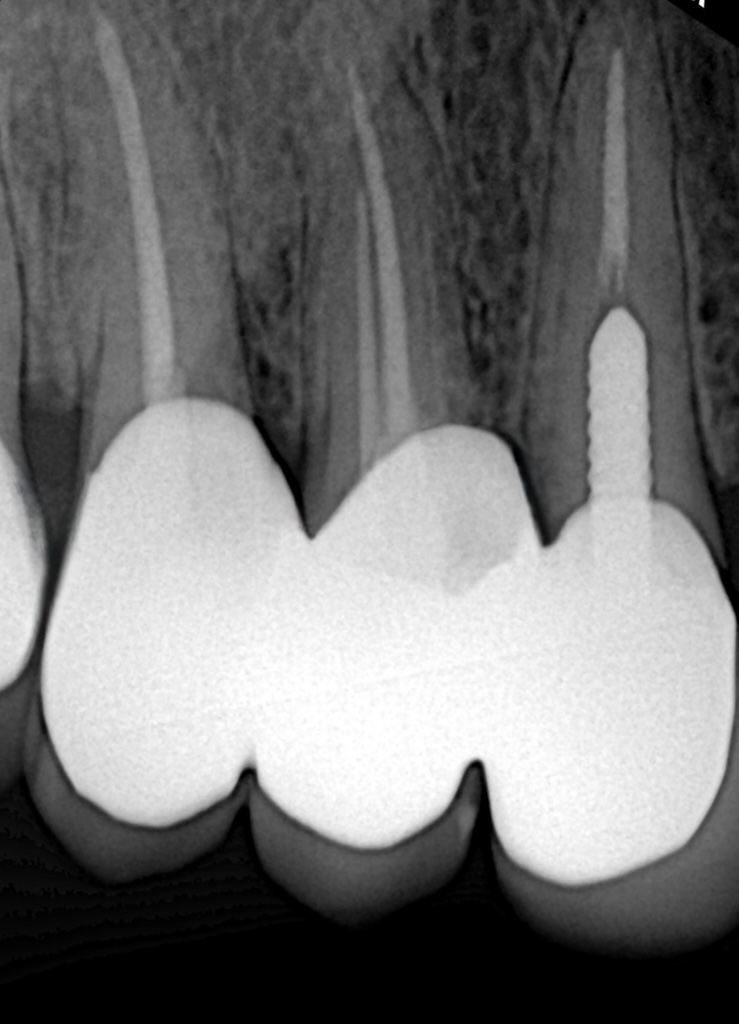

Radiographic Findings

- Previous endodontic treatment visible in UL3 and UL6

- Inadequate obturation and coronal leakage

- Widened PDL space on UL6

- Normal apical architecture on other teeth

- No sinus tract present

POST PLACEMENT

A ferrule assessment revealed compromised cervical strength in UL3 and UL6.

Both posts were adhesively luted to optimise retention and biomechanical reinforcement prior to core build-up.

| Tooth |

Post Type |

Rationale |

| UL3 |

Cast metal post |

Long clinical span, high retention requirement, anterior guidance involvement |

| UL6 |

Fibre post |

Better stress distribution, adhesive bonding, preserves root integrity |